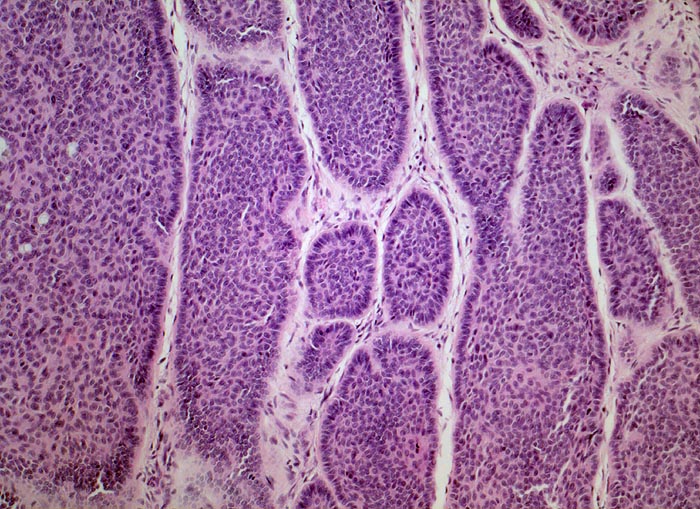

• Solide blaue Tumorzellplatten in der Dermis, teils mit Kontakt zur Epidermis.

• Die zytoplasmaarmen Tumorzellen ähneln Basalzellen der Epidermis.

• Palisadenförmige Anordnung der Tumorzellen am Rand der Zellplatten.

• Retraktionsartefakt zwischen Tumor und Stroma.

• Tumorstroma bestehend aus Fibroblasten, lockeren Kollagenfasern, hellblauen Muzineinlagerungen und chronischem Entzündungsinfiltrat.

• Im Zentrum einzelner Tumorzellplatten Verhornung, Tumornekrosen oder Hohlraumbildungen.